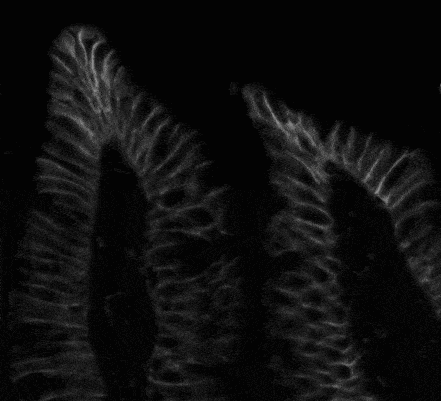

Fig. 3. DAPI fluorescent image

Watershed segmentation was applied to the DAPI images to obtain markers (labels) for the characterization of cells with nuclear accumulation of β-catenin.